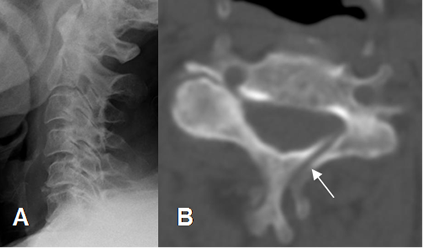

Las anormalidades en la alineación descritas incluyen: interrupción de las líneas intervertebrales anterior y posterior, de la línea espinolaminar, rotación de las apófisis espinosas, ensanchamiento de la distancia interespinosa e interpeduncular. (7, 39). (Fig 164, 165 y 166).

Fig 164. Desalineación.

Rx lateral. Anterolistesis post-traumática, con interrupción en las líneas intervertebral anterior y posterior.